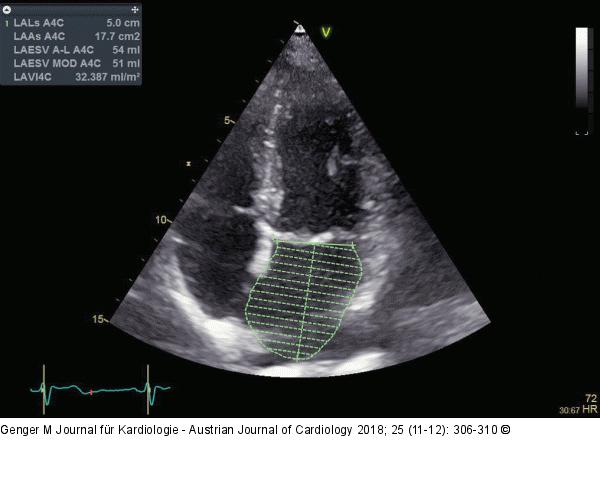

Abbildung 3: Linker Vorhof

Normal großer linker Vorhof (Volumenmessung am Ende der Systole unmittelbar vor der Öffnung der Mitralklappe) |